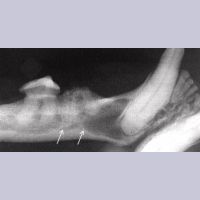

Image 7.18. Flap exposure for extraction

(적출을 위한 잇몸 절개?)

송곳니의 resorption 내부

Image 7.19. 봉합